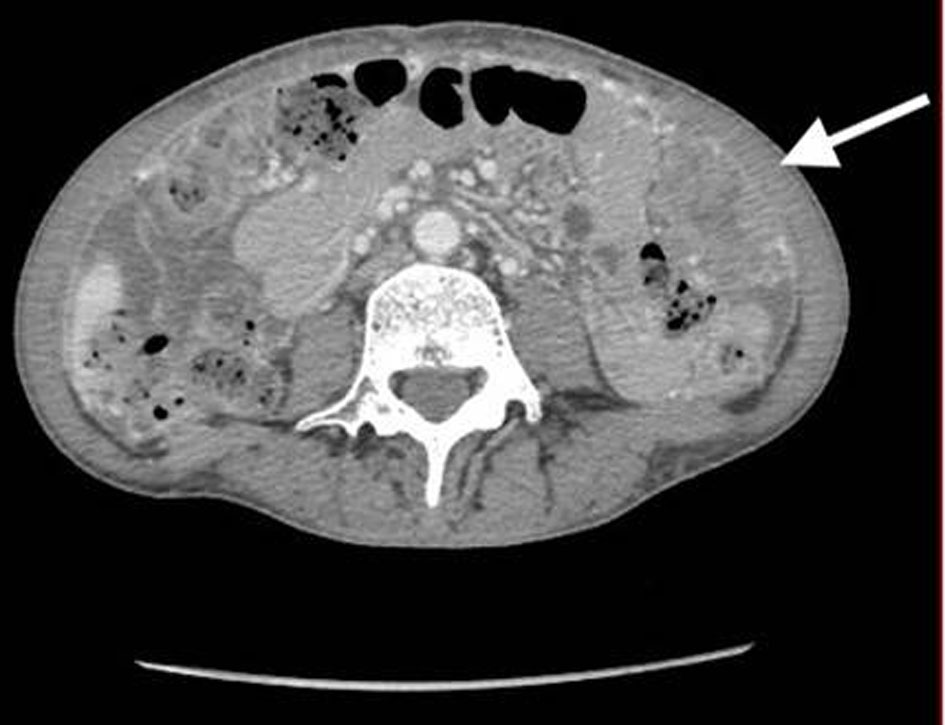

A 53-year-old, nulliparous, post-menopausal Asian woman presented with abdominal pain, distension, and heavy vaginal bleeding. She was diagnosed with stage III C ovarian carcinoma at an outside clinic. Ultrasound examination revealed a complex pelvic mass measuring approximately 13.5 × 12.3 × 9.8 cm. The largest cystic portion of the mass was posterior midline with irregular internal borders and papillary projections and measured 5.9 × 5.4 × 4.6 cm. Computed tomography (CT) scan demonstrated bilateral ovarian masses, ascites and carcinomatosis consistent with ovarian cancer (Figs. 1, 2). Her carbohydrate antigen-125 (CA-125) levels were 25 U/mL. She underwent a total abdominal hysterectomy with bilateral salpingo-oophorectomy with peritoneal tumor debulking for the widespread intra-abdominal disease.

![]() Click for large image | Figure 1. CT of abdomen and pelvis shows bilateral ovarian masses, and short arrow shows left ovarian mass. CT: computed tomography. |